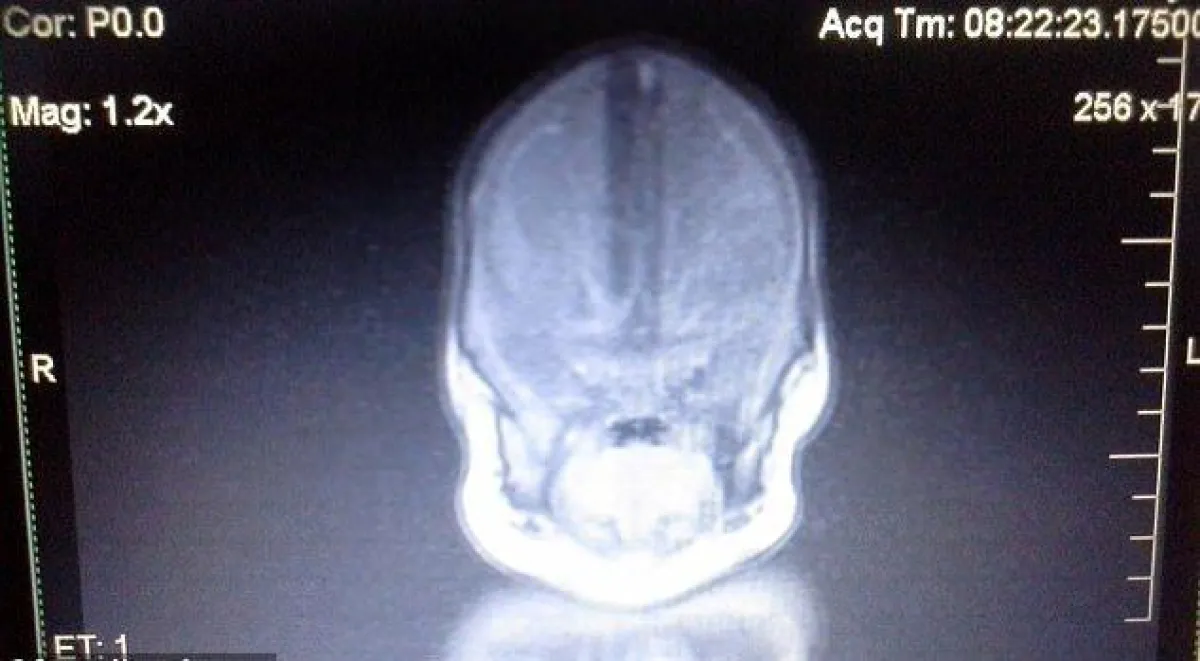

توجه الأطباء صوب العائلة التي تنتظر بدوامة من قلق، بوجوهٍ تحمل لوالدي "ليلي" جواباً مأساوياً، قال الطبيب: "نحن آسفون، هناك خبر سيء، ما وجدناه لم يره أحد على الإطلاق في هذه المستشفى، ليلي لديها جذع دماغ، ولكنها لا تمتلك دماغاً، ويظهر مكانه شكل كتلة من السائل"، و"ليلي لن تتمكن من الحديث أو الحركة أو إظهار العواطف تجاه أحد. ولن تستطيع التعرف على الأشخاص. وللأسف، تبقى لها في حياتها القصيرة، بضعة أشهر قليلة فقط لتعيشها". وأشار على الزوجين أخذها إلى المنزل، لتقضي الوقت القليل المتبقي لها هناك.

فشخص الأطباء إصابتها بهذا المرض النادر الذي يُصيب طفلاً واحد من بين 250 ألف طفل حديث الولادة في العالم، ويتسبب بوفاة الطفل المُصاب بعد أشهر قليلة. وأوضحوا أنه في هذه الحالة يكون نصف الكرة المخية، وهي القسم الكبير من أنسجة الدماغ الصلبة، مفقوداً تماماً، وتوجد سوائل مختلفة مكانه.

ويعتقد الأطباء أن السبب الرئيسي في حالة "ليلي"، هو أن دماغها خلال فترة الحمل، افتقد إلى الدم والأكسجين، ما تسبب بخثرة أو جلطة فيه. وتكوين كيس مليئ بسائل المخ والسائل الشوكي، بدلاً من وجود المخّ، القسم الأكبر من الدماغ. وأظهرت الصورة الضوئية وجود "جـذع المُــخ" الذي يتحكم بعملية التنفس والوظائف الحيوية للجسم، وبالإضافة إلى وجود المُخيخ المسؤول عن حركة العضلات.